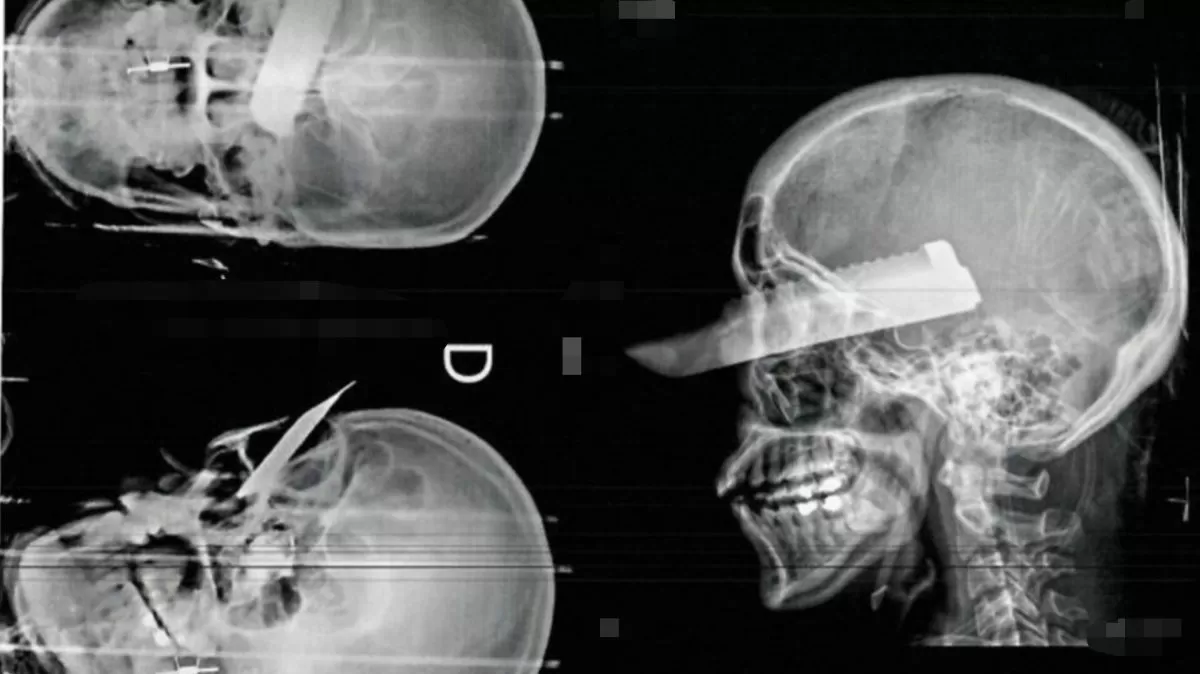

Durante a manhã, a violência atingiu um nível ainda mais assustador. O homem, visivelmente alterado, desferiu golpes com uma faca na direção da mulher. De acordo com a vítima, ele tentou acertar seu coração e sua garganta, mas ela conseguiu se defender e sofreu ferimentos nas mãos, braços e pescoço.

A mulher foi encaminhada para o hospital e passou por cirurgia para reparar os ferimentos causados pelo ataque. Segundo informações dos médicos, ela passa bem e não corre risco de vida.